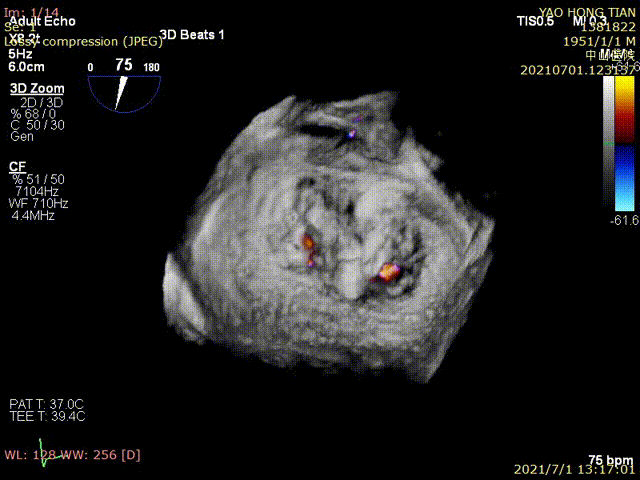

图1为一例患者的术前术后图像

术前超声